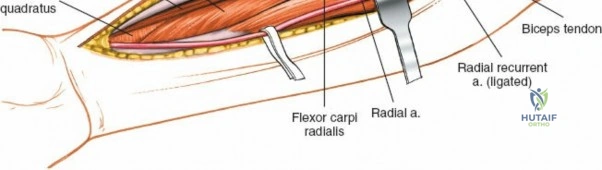

Managing the Radial Artery and Recurrent Leash

As the brachioradialis is retracted laterally, the radial artery and its venae comitantes are exposed lying deep in the middle part of the forearm, closely related to the medial edge of the wound. Begin dissection distally and work proximally. Just below the elbow joint, the radial artery gives off the recurrent radial artery and a leash of muscular branches that dive laterally into the brachioradialis.

This leash must be meticulously managed. Take time to isolate, ligate, and divide these vessels. Do not attempt to use electrocautery alone on the larger branches, and absolutely avoid blunt avulsion. Avulsion of these vessels from the main radial artery is a potent cause of difficult-to-control intraoperative bleeding and severe postoperative hematoma. Once the leash is divided, the brachioradialis can be fully mobilized laterally, exposing the deep muscular layer.

Exposing the proximal third of the radius requires extreme vigilance due to the proximity of the posterior interosseous nerve. The key anatomical landmark here is the insertion of the biceps tendon. Follow the biceps tendon distally to its insertion on the bicipital tuberosity of the radius. A small bursa lies just lateral to the tendon; incise this bursa to gain initial access to the proximal radial shaft. Because the radial artery lies superficial and medial to the tendon at this level, all deep dissection must remain strictly lateral to the biceps tendon.